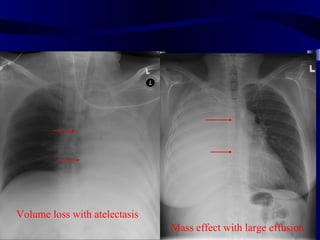

Volume loss with atelectasis

Mass effect with large effusion

50 y.o femalewith progressive SOB. What can you do to improve SOB?

Volume loss withatelectasis Mass effect with large effusion